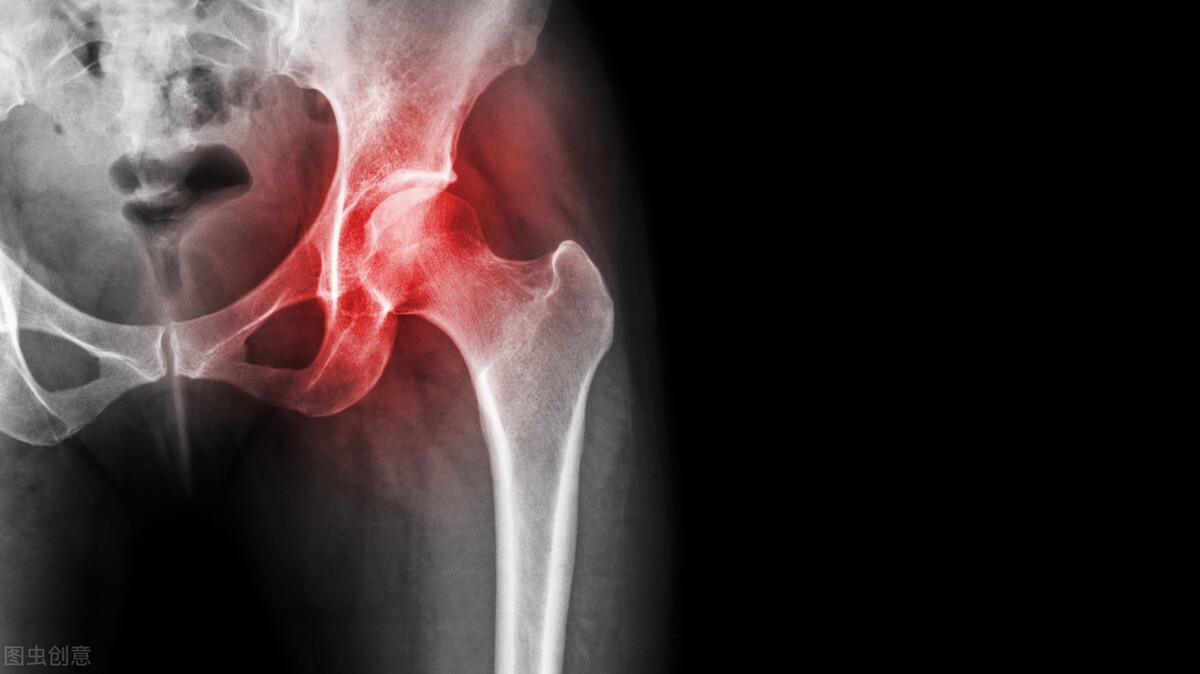

股骨颈骨折一般分为头下型,经颈型,基底型和混合型4种。头下型骨折发生坏死及不愈合的概率很高,尤其是股骨头发生的概率在所有类型里是最高的。骨折线越靠近大腿这个部位,发生坏死的概率越低。

总体来讲,股骨颈骨折,所有患者的股骨头发生概率约在30%左右。然后不同的类型发生概率不同,就像刚才我们所讲的有些类型甚至可以高达70%。